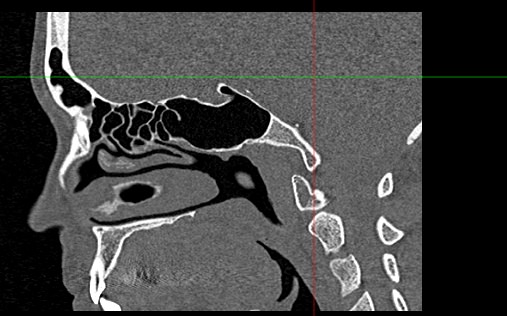

Золотым стандартом в диагностике патологических процессов пазух носа является мультиспиральная компьютерная томография, которая является быстрым безболезненным и неинвазивным (то есть без вмешательства в организм) способом исследования состояния синусов. Метод основан на проникающей способности ионизирующего излучения и получения изображений органов и тканей организма за счет разной степени поглощения ими рентгеновских лучей.

На основе полученных данных цифровые приложения томографов создают трехмерные реконструкции пазух носа, что позволяет оценить пространственное взаимоотношение анатомических структур и помогает в диагностике патологии околоносовых пазух.

Мультиспиральная компьютерная томография дает информацию о состоянии полости носа, носовой перегородки, степени воздушности околоносовых пазух, путей дренирования синусов, состоянии слезных каналов. Сканирование позволяет оценить толщину слизистой, наличие патологического содержимого в просвете пазух (уровня «жидкости»), выявить опухолевые образования. С помощью КТ можно провести точную диагностику травматических повреждений костей лицевого черепа, определить локализацию инородных тел, попавших в полости синусов.

С помощью объемной реконструкции можно перед оперативным вмешательством увидеть особенности анатомии ЛОР-органов, определить точное расположение патологического очага по отношению к окружающим тканям. Компьютерная томография помогает в диагностике аномалий развития придаточных пазух носа, слезоотводящих каналов.